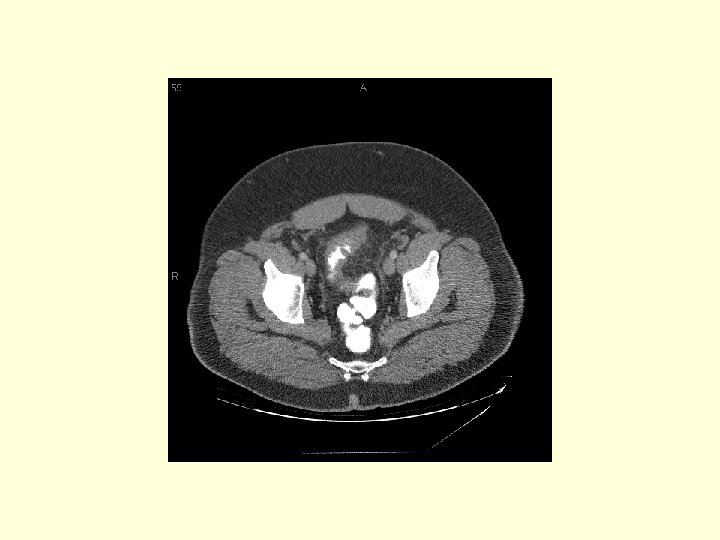

This is a patient with diverticulitis. Trace the sigmoid colon (white arrows) over the next 6 images and noted the wall thickening and the mesenteric fat stranding (circle).